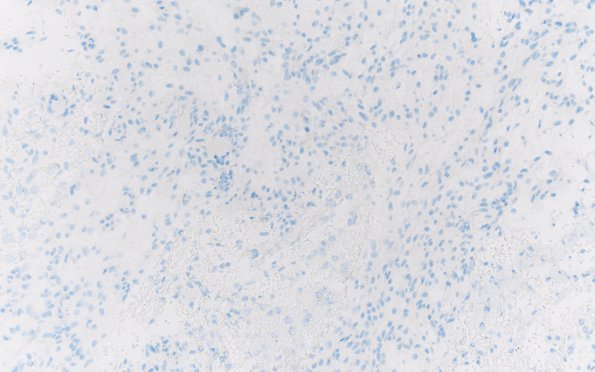

Washington University Experience | NEOPLASMS (GLIAL) | Angiocentric glioma | 8K Angiocentric glioma (Case 8) IDH1 20X 2

Mutant IDH1(R132H) is negative. (IDH1[R132H]) ---- Not shown: ATRX is retained. P53 shows wild-type staining pattern. Alcian Blue/PAS stain shows glial tissue with a small amount of mucinous material. BRAF V600E IHC is negative. ---- Comment: Analysis by Foundation One showed the presence of a MYB-QKI fusion gene, the primary driver mutation in this tumor type, and the key molecular feature characteristic of this tumor.